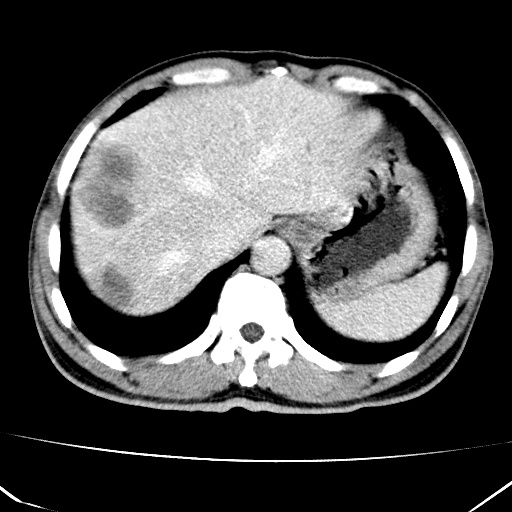

标题: CT17975:请求会诊。男、57岁。上腹部胀痛2天。临床诊断:糜 [打印本页]

标题: CT17975:请求会诊。男、57岁。上腹部胀痛2天。临床诊断:糜

肝脏多发类圆形低密度影,考虑肝脏转移瘤,肝胃韧带一淋巴结肿大,原发?胃癌?

考虑胃癌肝脏转移可能性大。

考虑胃癌并肝脏及腹膜后淋巴结转移;不排除淋巴瘤。

肝内转移瘤,腹腔及腹膜后淋巴结转移。